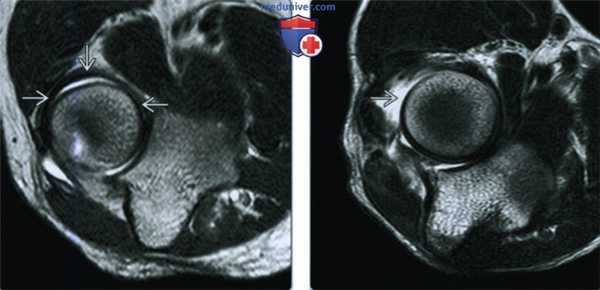

(Слева) На осевой MPT Т2 ВИ у этого же пациента определяется циркулярный тип кольцевой связки В на уровне головки лучевой кости.

(Справа) На осевой MPT Т2 ВИ виден разрыв кольцевой связки как части более диффузного повреждения комплекса латеральной коллатеральной связки локтевого сустава. В целом, повреждение кольцевой связки менее значимо, чем разрывы лучевой коллатеральной и латеральной локтевой коллатеральной связки.